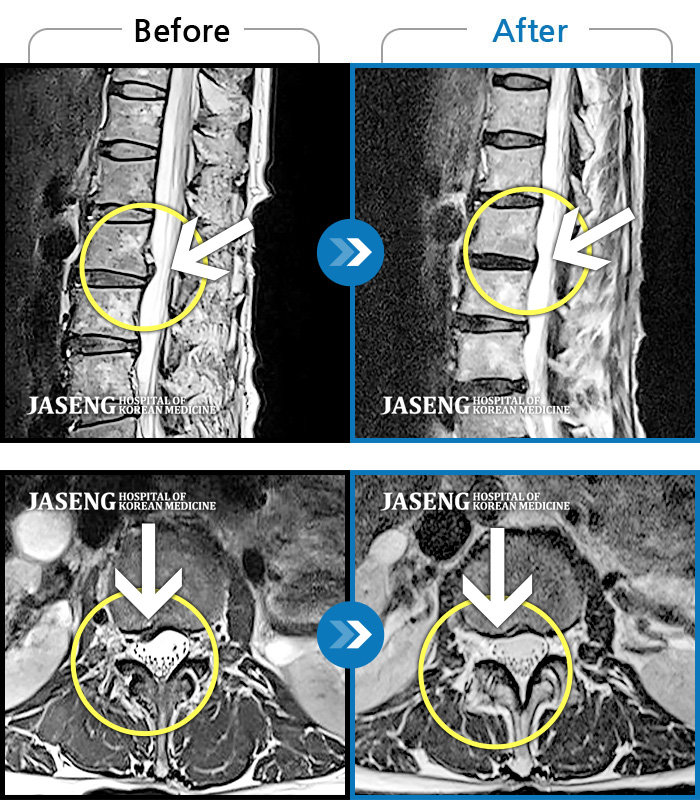

Before

After

환자에게 사전 동의를 받아 동일 조건에서 촬영되었습니다.

개인에 따라 치료 후 부작용이 발생할 수 있으니 의료진과 상담 후 치료를 진행하시기 바랍니다.

좌측 하요추부 통증과 좌측 둔부에서부터 대퇴까지 후면 저림

허리 우측 골반 통증, 2분만 걸어도 힘들고 자세 변경 시 통증 심화